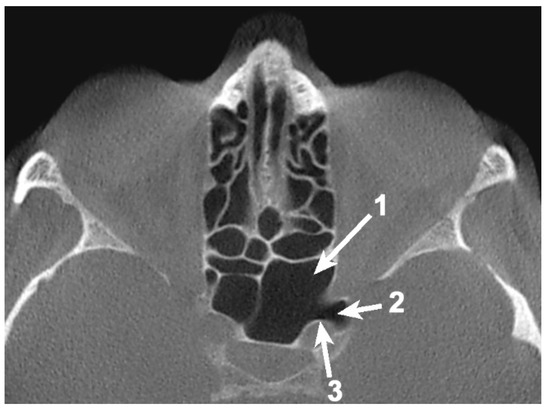

A total of 85 OS (53.12%) were pneumatized. The prevalence of OS pneumatization within the total was 67.5% (45 female and 9 male patients), 42.6% (23 cases) of them being unilateral (Table 1) (Figure 1 and Figure 2).

Figure 1. Axial CBCT slice at the level of the left anterior clinoid process (ACP), demonstrating the unilateral pneumatization of the ACP via the optic strut (OS) from the sphenoid sinus. 1. Sphenoid sinus; 2. Pneumatized ACP; 3. Pneumatized OS.